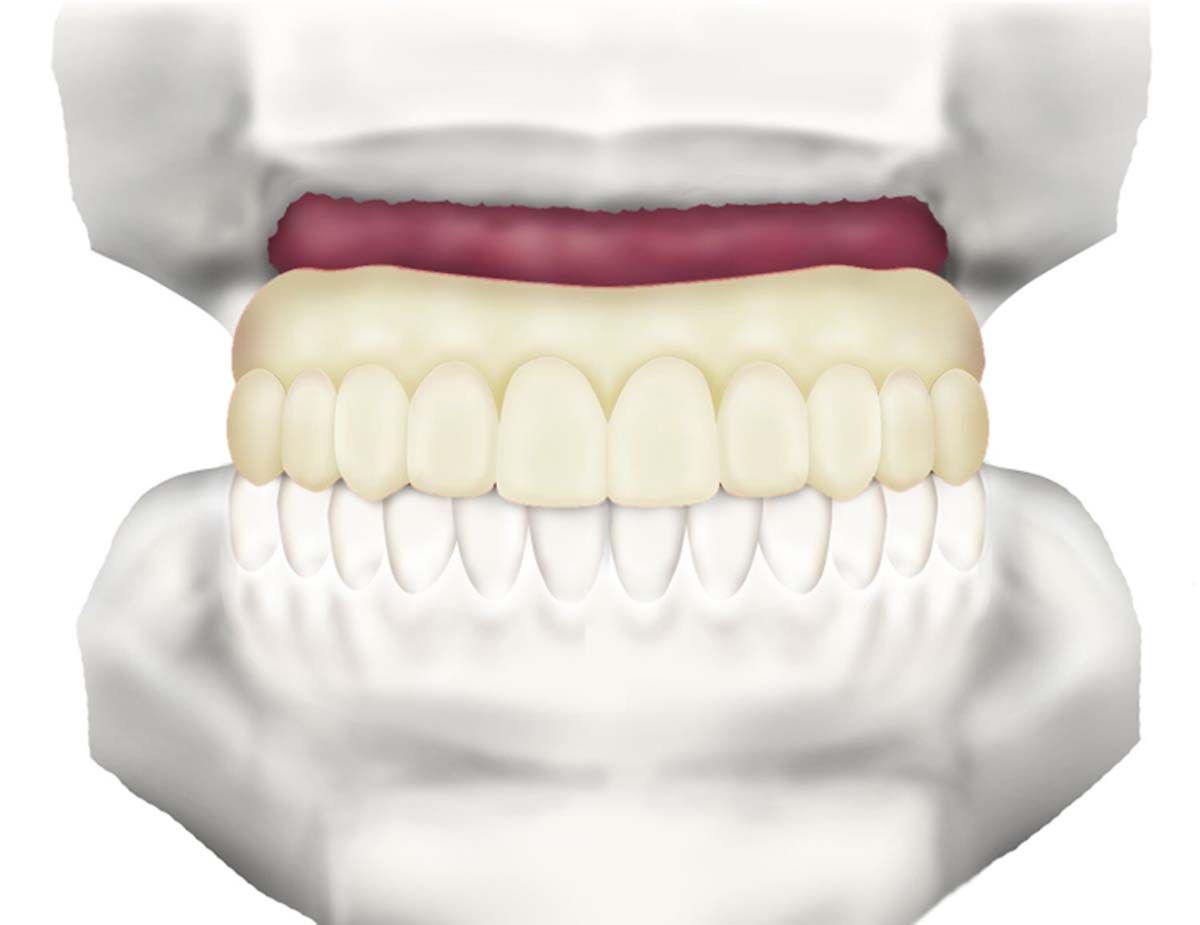

We used to try showing patients their clinical situation on 2D x-rays and demonstrating treatment using models. Later, digital intraoral cameras helped, but they could not show much more than what a patient could see in a mirror. Today, it is possible to show patients every angle of their clinical situation in hyperrealistic 3D with a CBCT scan. Now, when I recommend treatment to patients and they ask why, I am armed with an interactive image captured by my CS 8200 3D extraoral imaging system (Carestream Dental). I scroll through the tooth and bone, point out lesions below the surface, and show why there is or is not enough bone for an implant. If you use something like the Prosthetic-Driven Implant Planning module to automatically merge an intraoral scanner file with the CBCT scan, you create an even more accurate picture. How much easier is it for the patient to accept treatment when they are seeing the end results of that treatment?